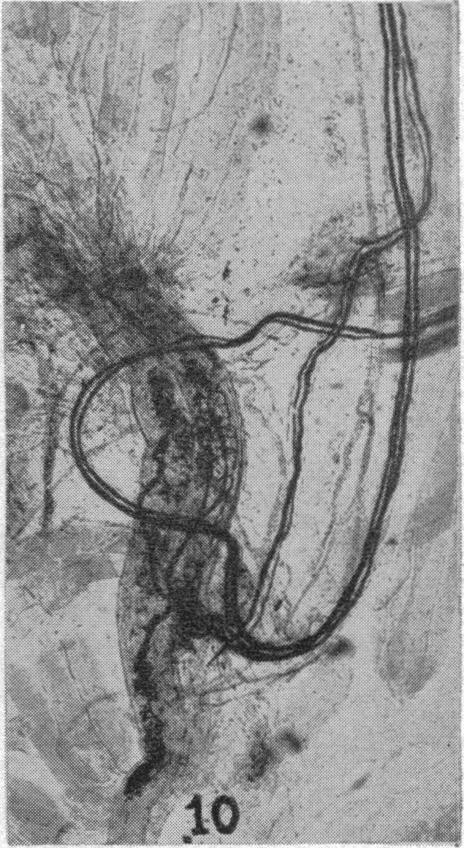

The innervation of skeletal muscle.

Br Med J. 1960 Mar 5;1(5174):671-4. doi: 10.1136/bmj.1.5174.671.